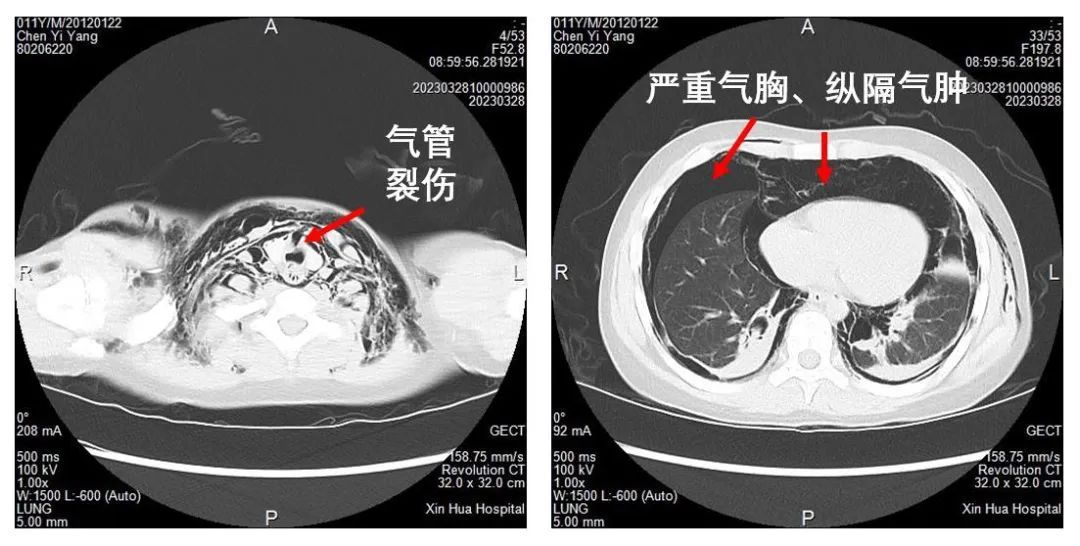

近日,男孩小阳(化名)在小区内骑自行车玩耍,被一条狗追赶,慌乱下撞到了小区内停放的卡车。由于孩子车速较快,这一撞撞得颈部、喉部都严重受伤。紧急送医后,当地医院胸部CT提示:纵膈气肿、颈部积气,建议转上级医院就诊。在转诊过程中,小阳出现左胸疼痛、胸闷的症状,血氧饱和度出现下跌,病情危急。

结合病史影像,新华医院儿急危重症医学科主任朱晓东、副主任朱月钮认为,小阳情况危重,进行性加重的气胸和纵隔气肿随时可能危及生命。于是,立即召集多学科床边会诊,制定治疗方案。就在专家会诊期间,小阳胸闷、气肿逐渐加剧、呼吸困难,新华医院儿普外科武志祥副主任医师立即在小阳的病床边紧急进行“胸部皮瓣引流和胸腔引流”,将孩子从悬崖边拉回。

孩子的生命体征稳定下来了,但问题出在哪?损伤源头的探查和修复是关键。危急时刻,耳鼻咽喉-头颈外科黄琦主任医师一锤定音,为小阳进行气道探查修补,并气管切开。在麻醉与重症医学科的全力支持下,孩子平稳地开始气道手术。术中情况证实了专家团队的预判,在甲状腺峡部深面气管右前方有一个大小约1cm的裂口,黄琦主任医师小心地修补了气管裂口,并留置了气管切开以便于恢复。